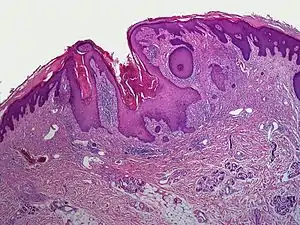

A dilated pore, also known as a dilated pore of Winer, is a cutaneous condition characterized by a solitary, prominent, open comedo on the face or upper trunk of an individual.[1]:675 Louis H. Winer is credited with discovering the dilated pore. [2][3]

| Dilated pore of Winer |